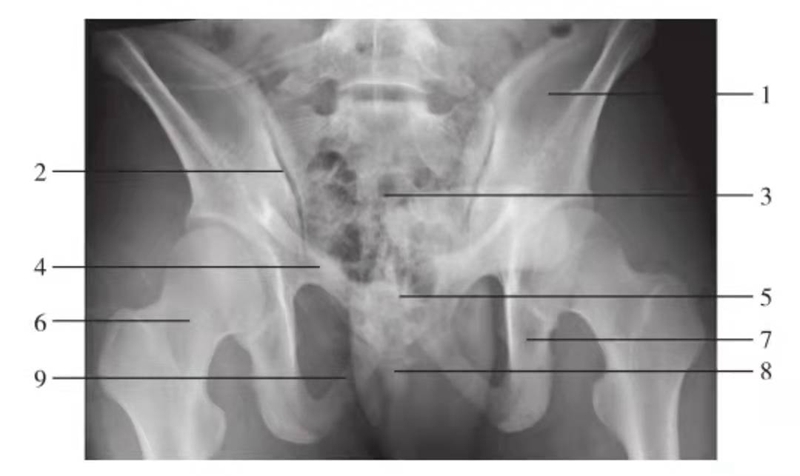

骨盆出口位

图8 骨盆出口位

1.髂骨翼;2.骶髂关节;3.骶骨;4.耻骨上支;5.耻骨联合;6.股骨颈;7.坐骨支;8.尾骨;9.耻骨下支